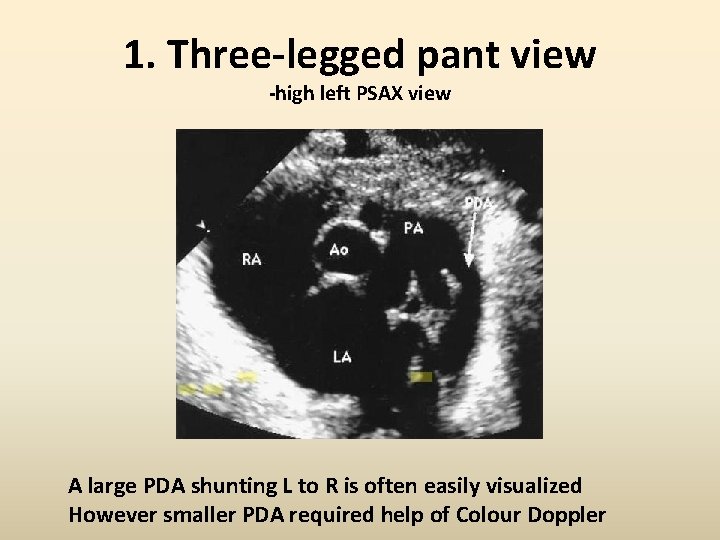

1. Three-legged pant view -high left PSAX view A large PDA shunting L to R is often easily visualized However smaller PDA required help of Colour Doppler